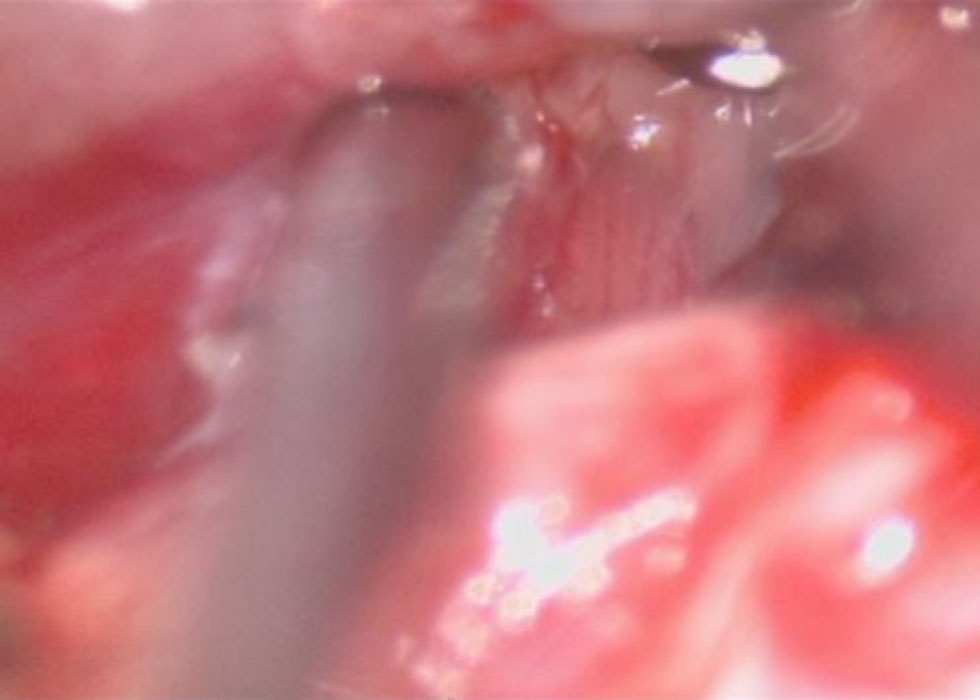

No.’25_108  摘出 中